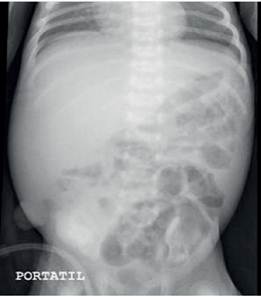

En el post operatorio inmediato recibió transfusión de paquete globular (15cc/kg) y se rotó la cobertura antibiótica a Imipenem (25mg/kg/do), Vancomicina (10mg/kg/do) y Metronidazol (15mg/kg de carga, luego 7.5mg/kg/do), los mismos que completaron un esquema de 14 días. Así también, se inicia nutricional parenteral, sin aporte enteral durante los siguientes cinco días, al cabo de esto muestra evolución clínico - laboratorial favorable y radiografía de abdomen con disminución de neumatosis y buena distribución de aire (Fig N°2.), reiniciándose la vía enteral con leche materna exclusiva de forma progresiva, sin embargo, a los dos días presenta deposiciones líquidas y distensión abdominal, suspendiendo el aporte enteral programado y decidiendo cambiar a fórmula extensamente hidrolizada durante 10 días con evolución favorable. Por ello es programado a cirugía de restitución de tránsito intestinal, quedando 5 días sin aporte enteral para la cicatrización de anastomosis, al término se inicia el aporte enteral progresivo con leche materna, presentando al tercer día regurgitaciones biliosas en 3 ocasiones, distensión abdominal, deposiciones abundantes semilíquidas, fiebre 38,5°C y PCR: 28.8mg/dL; razón por la cual, se reinicia la fórmula extensamente hidrolizada normalizando los reactantes de fase aguda y con mejoría clínica notoria. Es dado de alta para seguimiento ambulatorio.